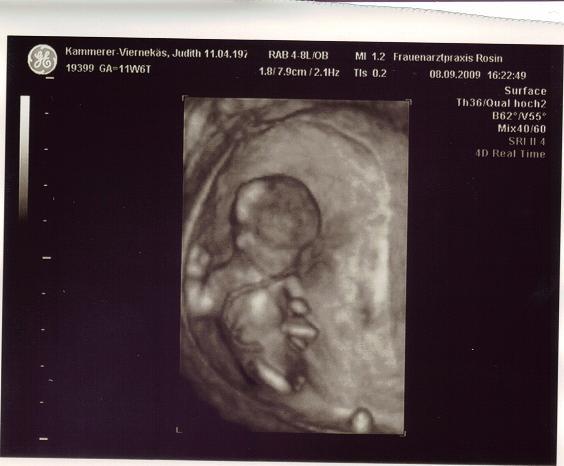

Hallo! Wir hatten heute unseren FA-Termin. Unser kleines Krümelchen war richtig aktiv und aufgeweckt und ist 6 cm groß. Der Arzt hat festegestellt, dass alles i.O. ist auch die Nackenfaltenmessung (bin 38) war optimal :o)) Unser ET-Termin wurde sogar eine Woche vorverlegt und ist jetzt der 18. März 2010. Wir sind richtig happy. Anbei ein Bild vom Baby. LG Judith

Bild zu Neues vom Baby - Forum für März - Mamis

Wowww, tolles Bild. Bin immer wieder von der 4D Qualität begeistert! Was hat das Baby denn da zwischen den Beinchen? Sieht das nach Junge oder Mädel aus ;-) ? Alles Gute weiterhin! LG Khadi

Hi! Ja, richtig ... da haben wir auch kurz überlegt .... sind aber eher die Zehen vom Füßchen LG Judith

Also für mich sieht das sowas von ganz klar nach einem Bub aus... Zehen sind das doch net, der Fuß ist doch ganz woanders auf dem Bild... hihi lg Manu